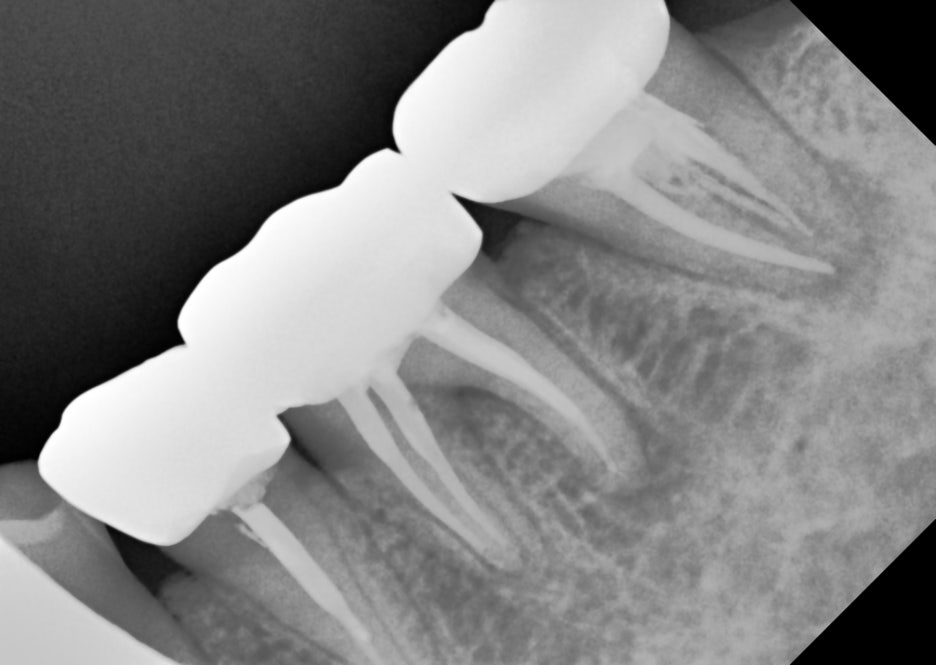

1. 신경관을 놓친 경우 (미싱 캐널, Missing Canal)

모든 치아 뿌리에는 한 개 이상의 **신경관(근관)**이 존재합니다.

특히 작은 어금니나 대구치에는 두 개 이상의 신경관이 존재할 수 있어요.

✅ 첫 치료 시 신경관을 놓쳤다면?

➡️ 해당 신경관에서 염증이 재발할 수 있습니다.

➡️ CT 등 정밀 검사로 미처 발견하지 못한 신경관을 찾아내면,

재신경치료로 회복 가능성 높음!

이런 경우는 오히려 명확한 원인을 찾을 수 있어

재치료의 예후가 긍정적입니다.